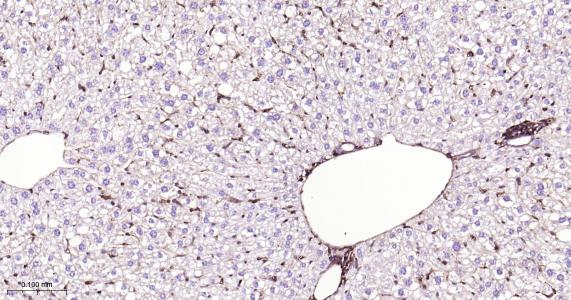

Paraformaldehyde-fixed, paraffin embedded Rat Liver; Antigen retrieval by boiling in sodium citrate buffer (pH6.0) for 15 min; Antibody incubation with CRMP2 Monoclonal Antibody, Unconjugated(bsm-61800R) at 1:200 overnight at 4°C, followed by conjugation to the bs-0295G-HRP and DAB (C-0010) staining.